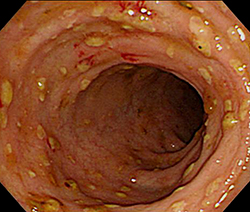

장염에 좋은 음식 10가지에 대하여 정리해 보겠습니다. 장염은 위장 내키티스로서, 장의 염증으로 인하여 설사, 복통, 구토 등 각종 증상을 같이할 수 있는 질병이고요. 장염을 앓고 있는 사람에게는 공정한 식단 절제이 굉장히 주요합니다.